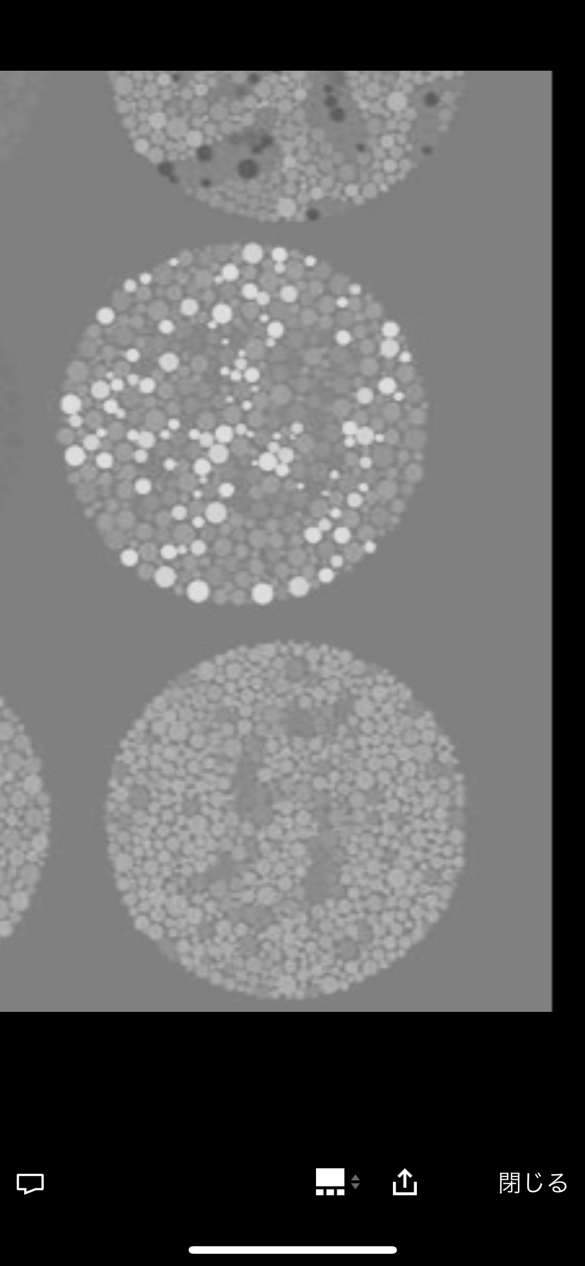

【画像】この画像の右下が読める奴、ガチでやばいぞwwww

6.12.73

15.2925

これ読めないって目大丈夫か?

6 12 73

15 29 ?

36: 風吹けば名無し 2022/08/04(木) 20:58:04.35 ID:BeQxCFZL0

>>14

これが正常者の答えな

右下トラップ見える人には何が見えるんやろ

右下見める奴は色弱定期

15を17に

左下が17、下が70に誘導させたがってるのはわかるんやが、右下は何に見えるのか検討もつかん

45: 風吹けば名無し 2022/08/04(木) 21:01:30.64 ID:KXF2S5DE0

ググったら一部の人には5が見えるらしい

右下は見える人には5に見えるんか?

赤と緑が全く区別できん人には見えるらしいで

国際版石原式色覚検査

『全部読めた人は色覚異常です』

『下段右が「5」に見える人は緑系の色覚異常です』

ガチの色弱判定者だけど右下は8に見える